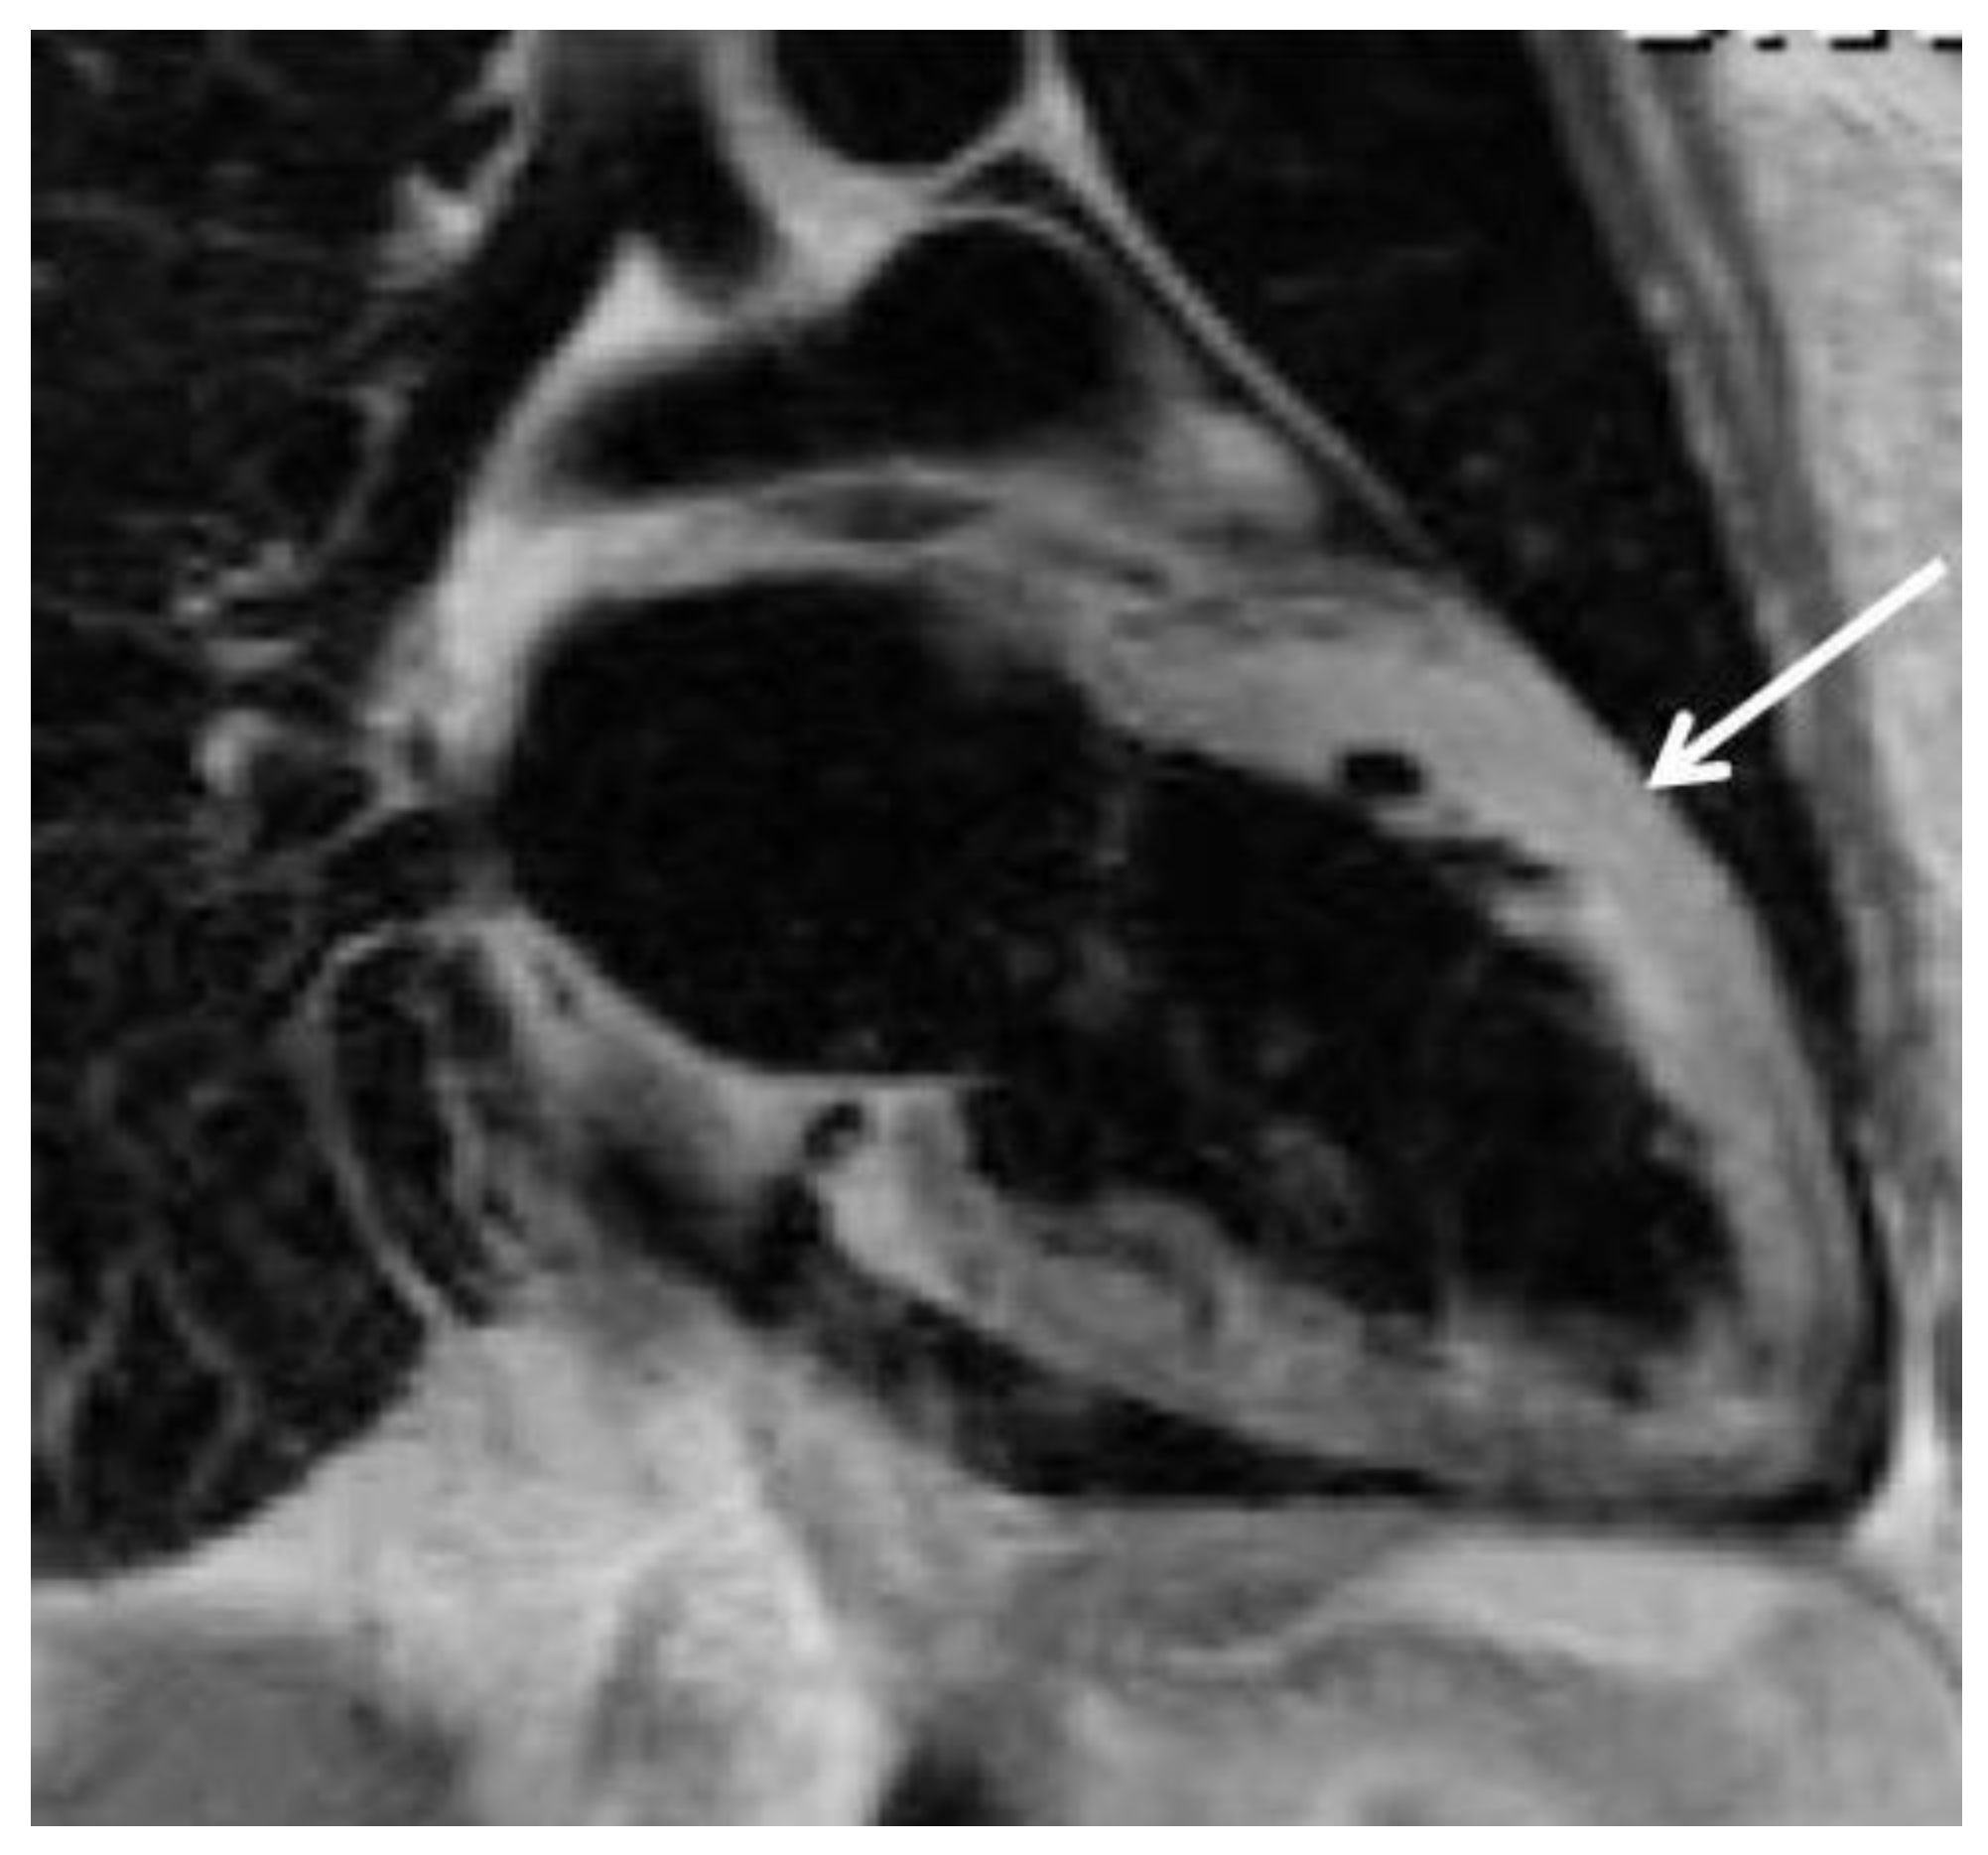

Peripartum cardiomyopathy (PPCM)